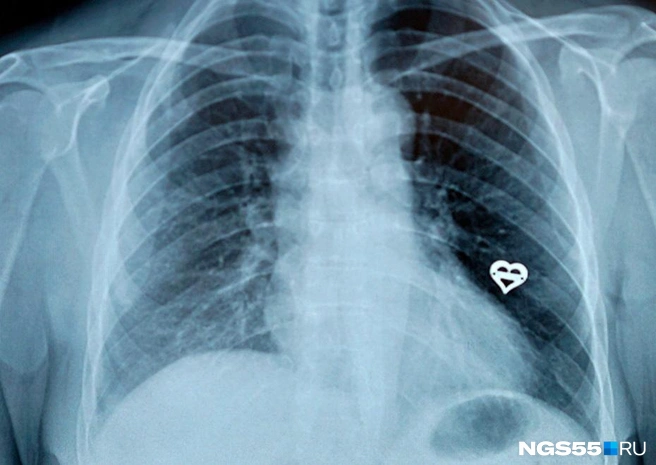

— Томография показала достаточно крупное твёрдое тело. Тут какие варианты — оперировать и удалять часть лёгкого, уменьшая дыхательный объём, или извлечь с помощью фиброэндоскопа, — рассказывает Альгис Хасанов.

Процедура выглядит так: через нос в дыхательные пути вводится фиброэндоскоп — через него и смотрят, им же и манипулируют. Дело осложнялось тем, что зуб к этому моменту уже месяц лежал в лёгком и потому успел обрасти отложениями. Кроме того, по меркам дыхательной системы это всё-таки достаточно большой объект. Но зуб со второй попытки удалось вытащить манипулятором — подняли до рта, а там пациент уже смог его выплюнуть. Неприятная процедура, да. Но перспективы распластанного лёгкого и последующей инвалидности никак не лучше.

Если простым языком — через прокол в груди хирург вводит эндоскопические инструменты в полость тела и проводит операцию. Через другой прокол вводится специальная видеокамера с фокусировкой и вспышкой — темно внутри! — и транслирует изображение на монитор. Хирург, соответственно, делает свою работу, глядя на экран. Это называется видеоскопической резекционной операцией.